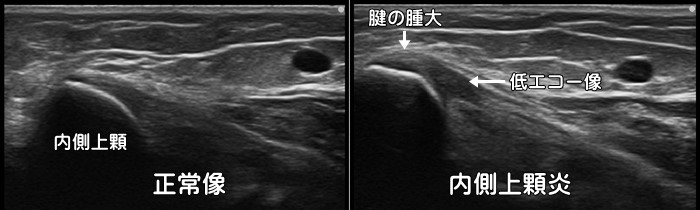

内側上顆炎・ゴルフ肘

肘の内側に痛みがあれば内側上顆炎(ゴルフ肘)が疑われます。エコーでは付着部の低エコー像が見られます。テニスのバックハンドでは外側上顆炎をフォアハンドでは内側上顆炎を発症します。